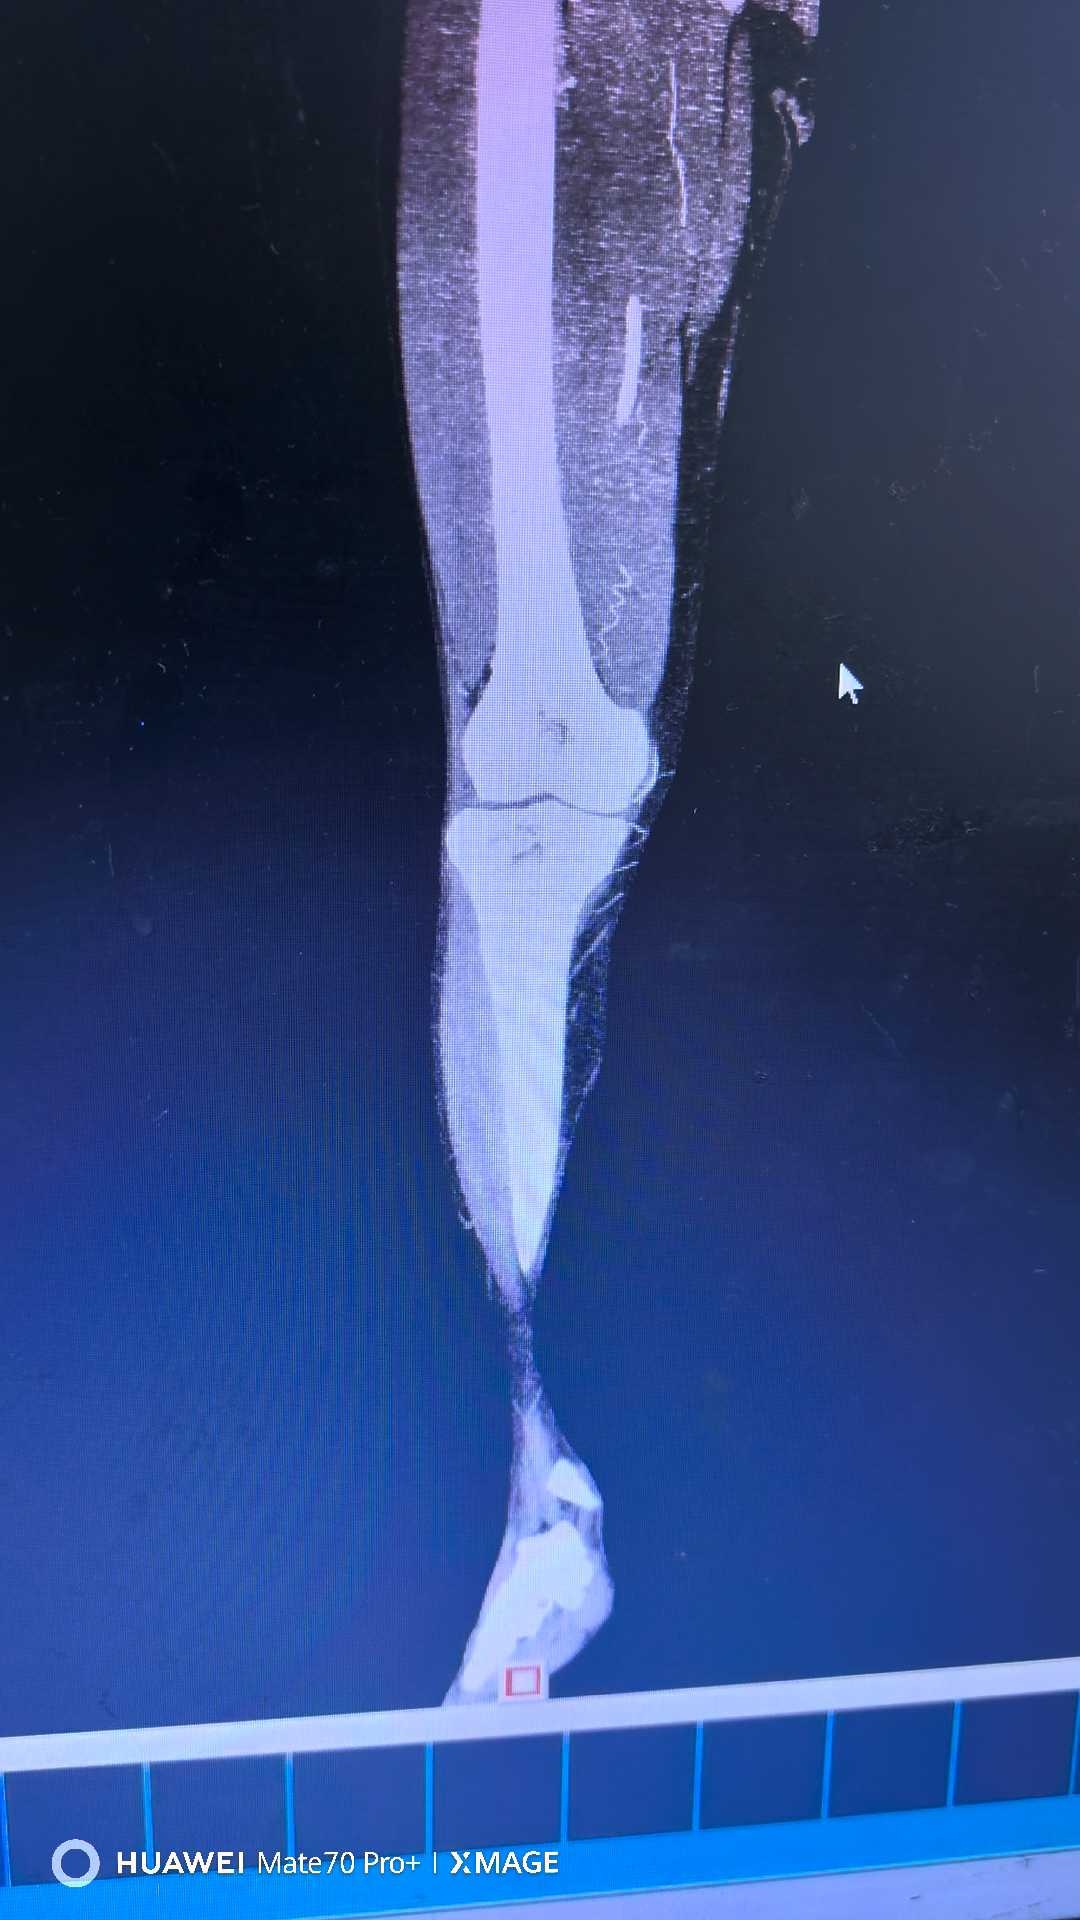

【检查】:

【临床诊断】:右下肢动脉闭塞(腘窝段)